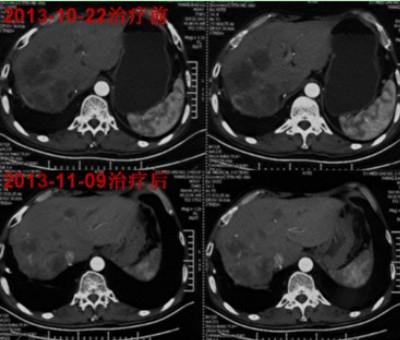

通过WB-1无创全身热疗系统,Echols先生病灶明显减少,绿色无毒,无创伤。随后进行了2个疗程的WB-1无创全身热疗系统治疗,Echols先生胀痛完全缓解,大便恢复正常,精神食欲明显好转,体重增加1公斤,影像检测转移灶减少了8个,肿瘤发展完全被控制,实现了长期的带瘤生存。